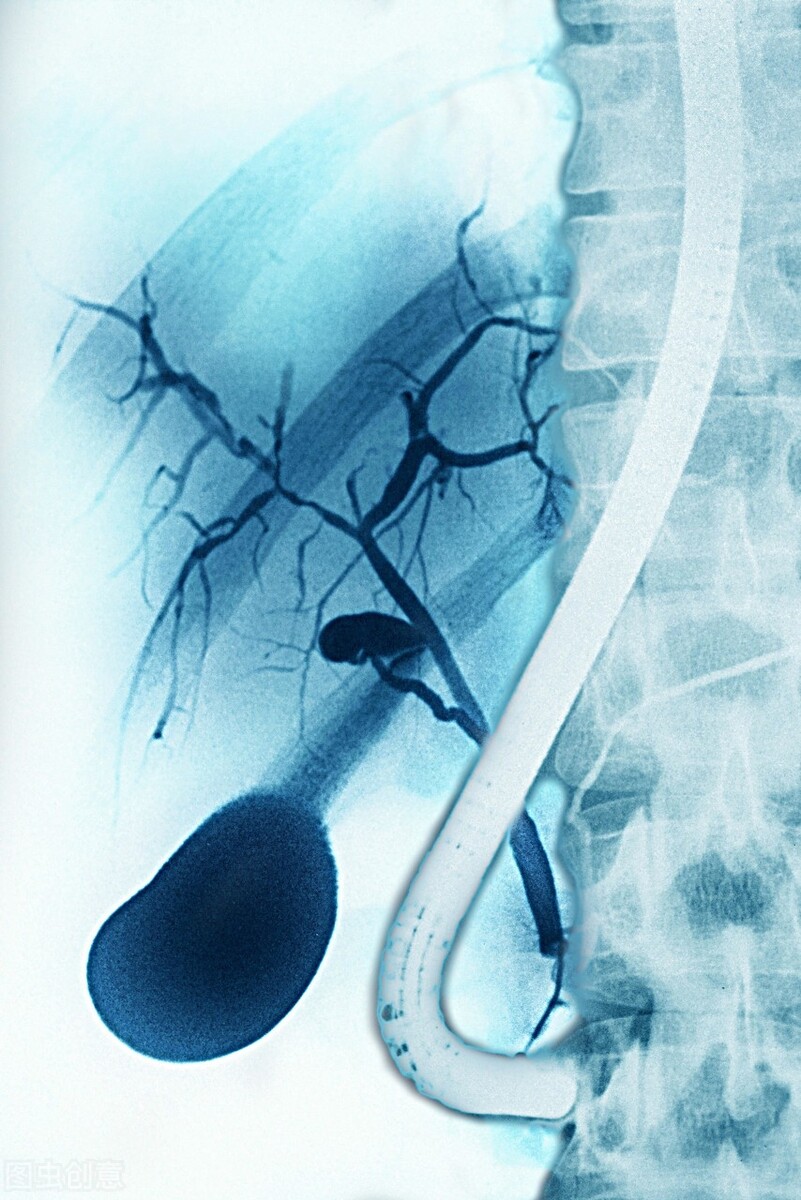

我们正常的胆囊,从肝内的胆管,就是肝总管,包括和胆囊管一起向下排,排出来叫胆总管。 当胆总管下面发生了堵塞之后,胆囊内部的这些管道里头又形成了炎症,包括脓汁和感染的物质以后,不能够从胆总管向下排,这时候形成的是结石或胆总管本身的一些疾病,这些化脓性的胆汁不能够排到肠道内,向内部形成高压,造成了整个胆道内的扩张。

这种情况不及时解除梗阻,只是抗感染,实际是不行的,一定要在第一时间通畅梗阻的胆道,把这些化脓的胆汁排出来。这种情况一般可以做手术,有的直接可以做穿刺,我们叫PTCD,就是经过体表穿刺,穿到扩张的胆管内把脓汁引出来,然后通过抗感染和抗休克治疗才把病人能够救过来。